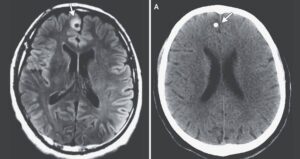

A Boston Man Started Having Mysterious Seizures — Then Doctors Discovered A Decades-Old Tapeworm In His Brain

The unnamed patient emigrated from a rural area of Guatemala where he may have picked up a tapeworm 20 years ago.